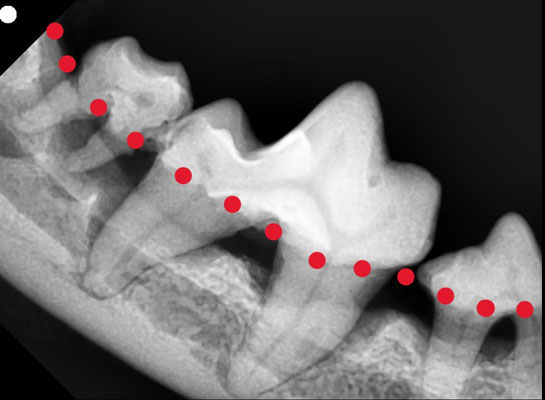

上のレントゲン写真は、犬の奥歯を撮影したものです。

1枚目(異常):赤い点線より下の部分は本来骨がしっかりとあるはずですが、歯周病によって骨が溶け、歯が支えられなくなっています。

歯科レントゲンを撮ることで、外からは見えない歯の根や骨の状態まで確認できるのが大きな特徴です。

目に見えない「歯周病の進行度」を把握できる

歯の根や周囲の骨の状態が分かる

抜歯が必要かどうか、治療の判断材料になる

見た目だけでは「歯石がついているか」しか判断できませんが、レントゲンを撮ることで本当に治療が必要な歯がどれかを明確にできます。